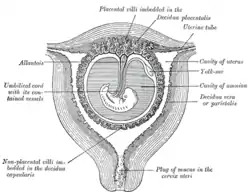

Sectional plan of the gravid uterus in the third and fourth month

Sectional plan of the gravid uterus in the third and fourth month Fetus in utero, between fifth and sixth months.

Fetus in utero, between fifth and sixth months. Female pelvis and its contents, seen from above and in front